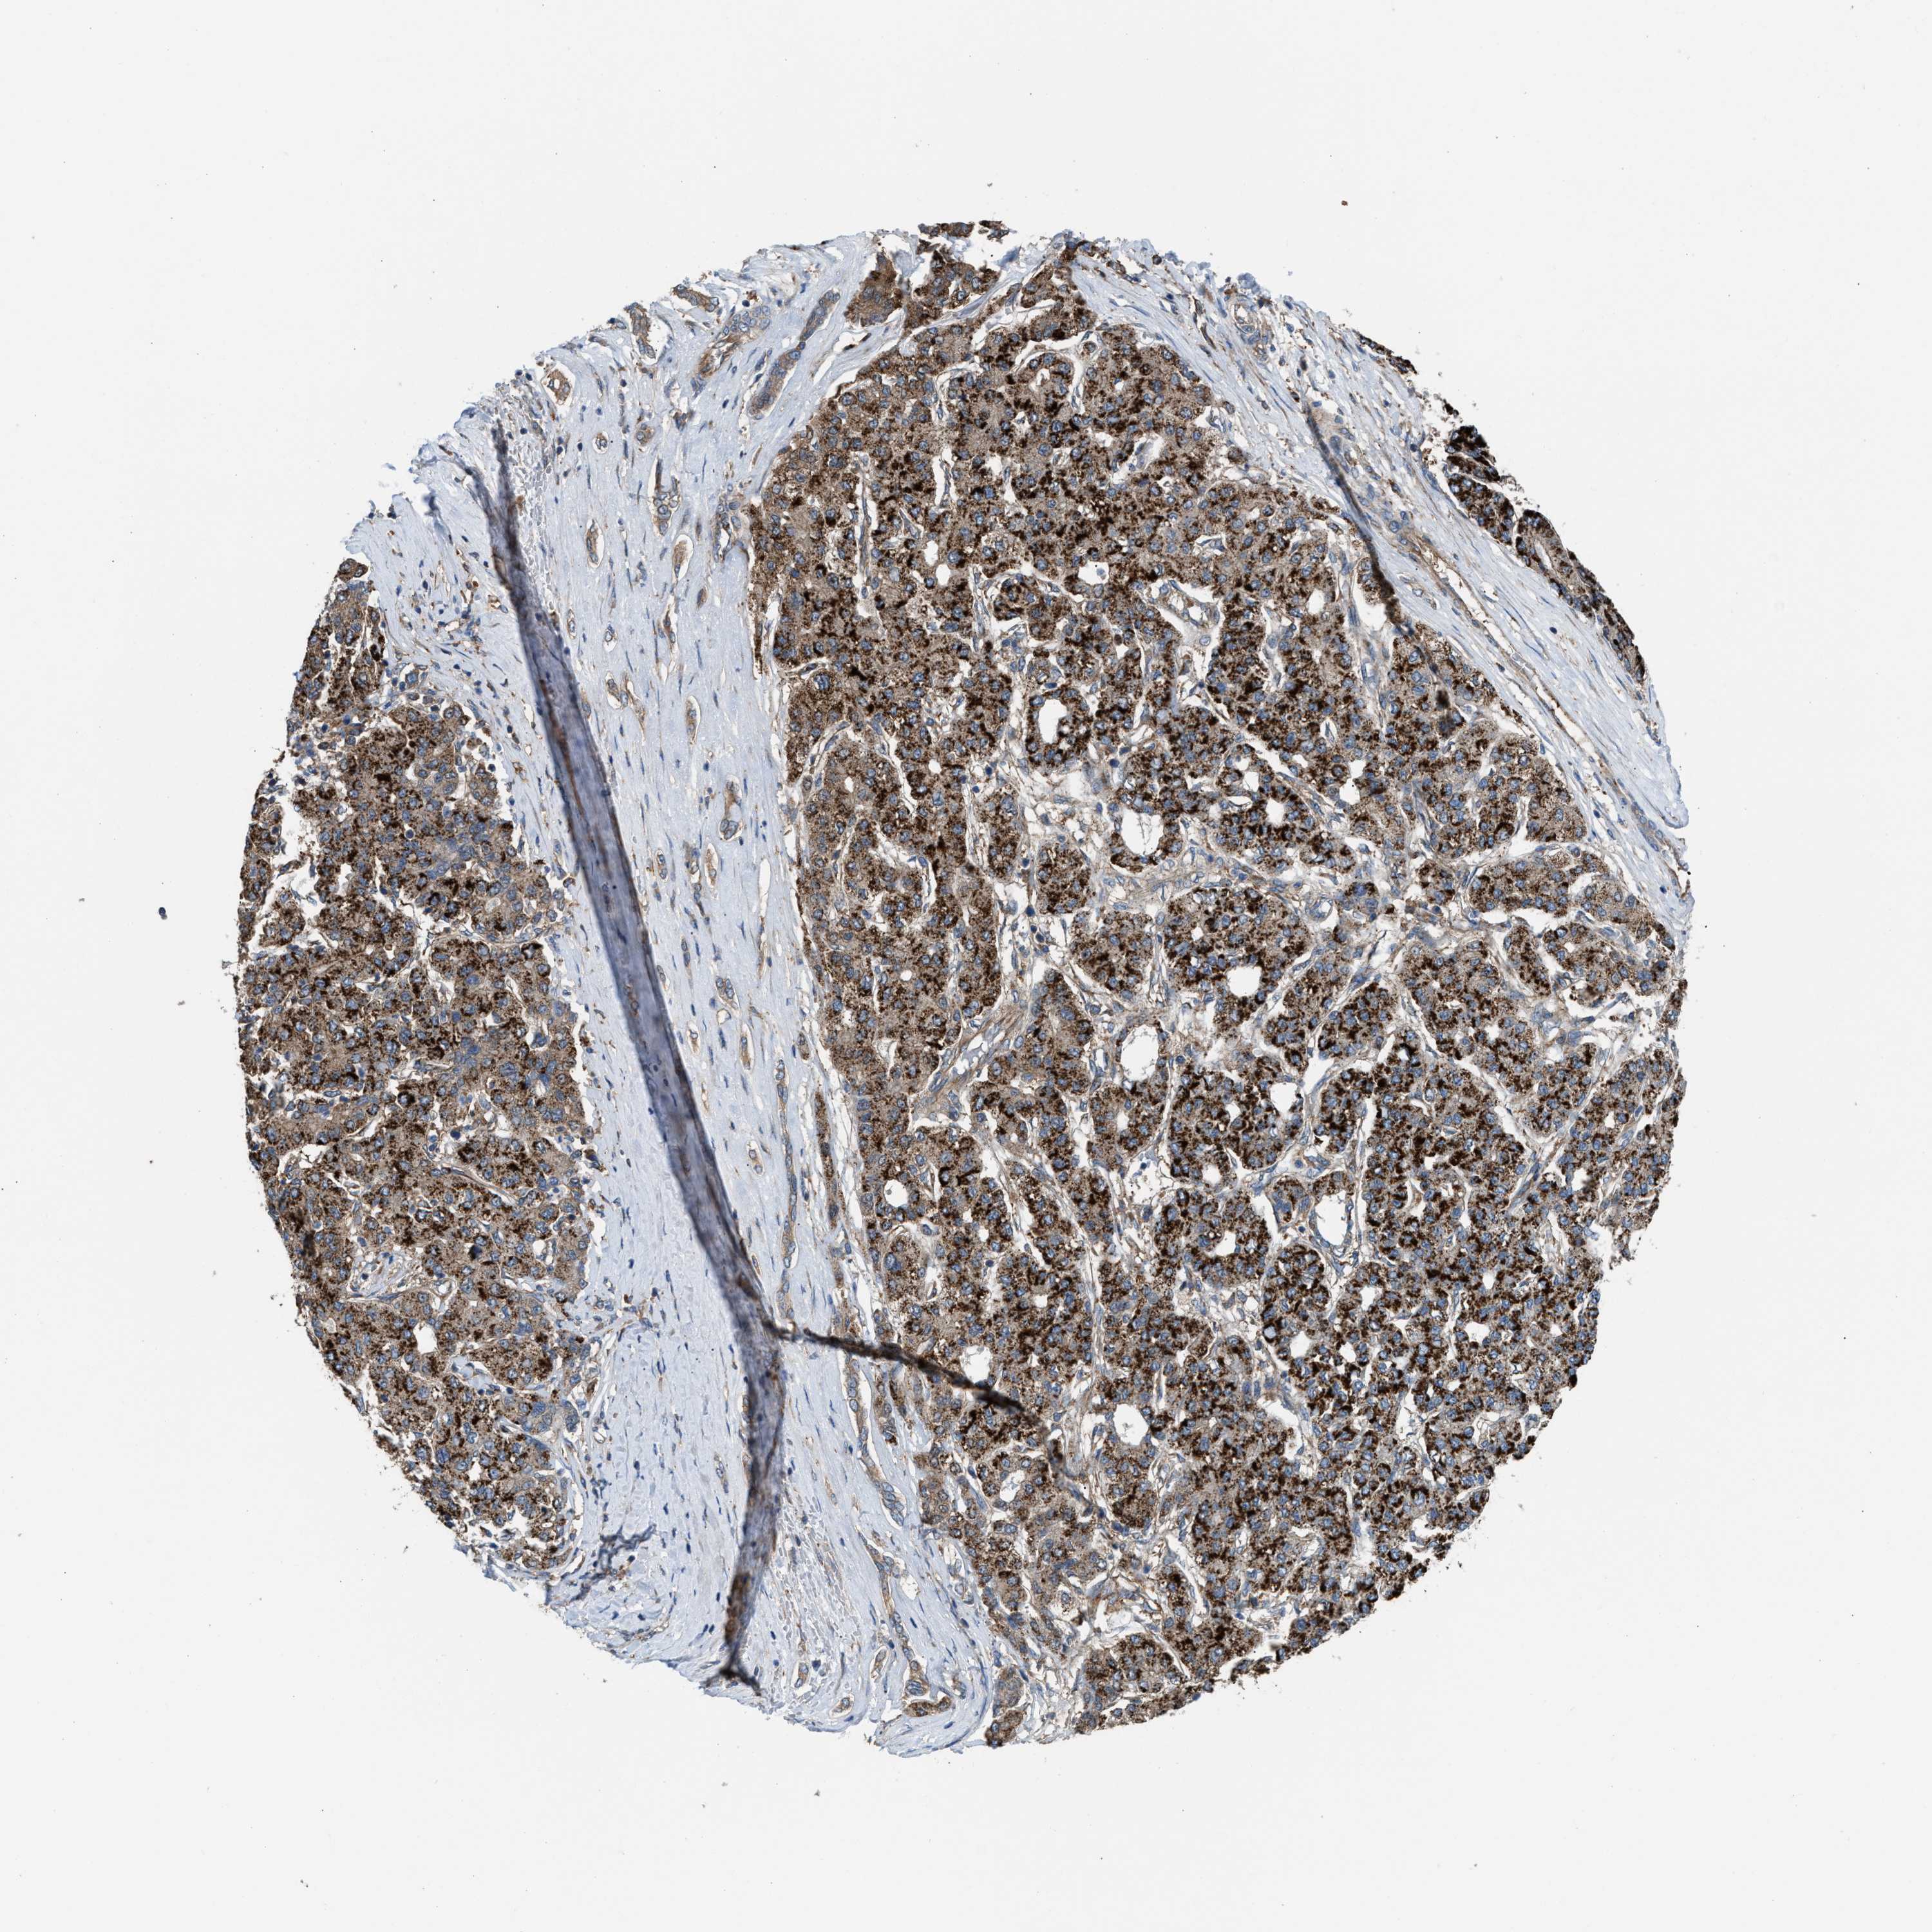

LIVER CANCER - Protein expressioni

A mouse-over function shows sample information and annotation data. Click on an image to view it in a full screen mode. Samples can be filtered based on level of antibody staining by selecting one or several of the following categories: high, medium, low and not detected. The assay and annotation is described here.

Note that samples used for immunohistochemistry by the Human Protein Atlas do not correspond to samples in the TCGA dataset.

Antibody stainingi

Antibody staining in the annotated cell types in the current human tissue is reported as not detected, low, medium, or high, based on conventional immunohistochemistry profiling in selected tissues. This score is based on the combination of the staining intensity and fraction of stained cells.

Each image is clickable and will lead to virtual microscopy that enables deeper exploration of all samples and also displays staining intensity scores, fraction scores and subcellular localization as well as patient and tissue information for each sample.

Antibody HPA021197

Staining

High

Medium

Low

Not detected

Intensity

Strong

Moderate

Weak

Negative

Quantity

>75%

75%-25%

<25%

None

Location

Nuclear

Cytoplasmic/membranous

Cytoplasmic/membranous,nuclear

Cholangiocarcinoma

Carcinoma, Hepatocellular, NOS